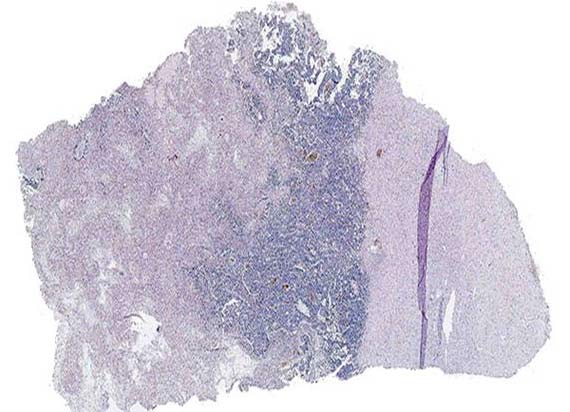

Visualize Panoramic images of the complete slide area

Creation of high quality digital slides. Exceptional quality, high definition and accurate color rendition thanks to Plan Apochromat objectives.

Immersion scanning with high magnification and high definition

Sample scanning with high magnification (60x, 100x), when the high quality of images is required. For example, for blood and bone marrow samples.

Optional Special high definition objectives are used for immersion scanning. These objectives work with immersion oil.